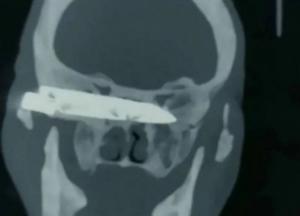

Мужчина 26 лет жил со ржавым ножом в голове прежде, чем его достали хирурги (фото)

Проживающий в деревенской местности китайского округа Хайан пожилой мужчина по имени Дуорици рассказал, что в 1994 году во время ограбления преступник вонзил ему в голову, возле глазницы, десятисантиметровый нож. Врачи местных больниц не брались проводить сложную операцию по его извлечению, так как она была опасна для жизни пациента. И фермеру пришлось оставить все, как есть — хотя его мучили сильные головные боли. Со временем он также ослеп на правый глаз и у него развился почти полный паралич конечностей с левой стороны, передает FaceNews.ua.

В конце концов его случаем заинтересовались два приезжих хирурга. Дуорици доставили в больницу провинции Шаньдун и бесплатно прооперировали. Сначала в ходе двухчасовой операции врачи благополучно извлекли из головы пациента лезвие. А спустя шесть дней провели еще одно хирургическое вмешательство, чтобы очистить рану. В настоящее время пациент благополучно поправляется. Он уже самостоятельно ходит, а его зрение восстановилось.

«Раньше я не мог смеяться, зевать и даже кашлять. Доктора дали мне шанс на новую жизнь и положили конец кошмару, который длился больше 20 лет», говорит он.